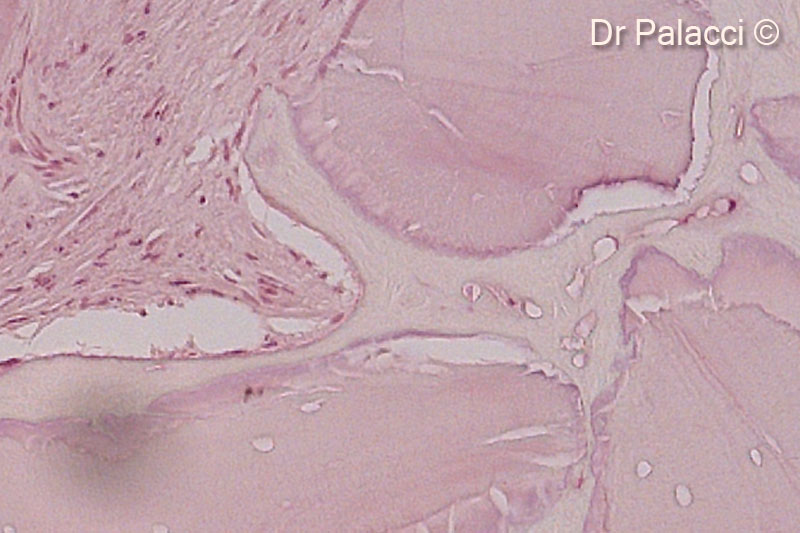

Một phần mẫu sinh thiết được lấy 4 tháng sau khi tăng cường bằng GTO. Các hạt vật liệu sinh học được bao quanh bởi xương mới hình thành, có sự hiện diện của các hốc tế bào xương